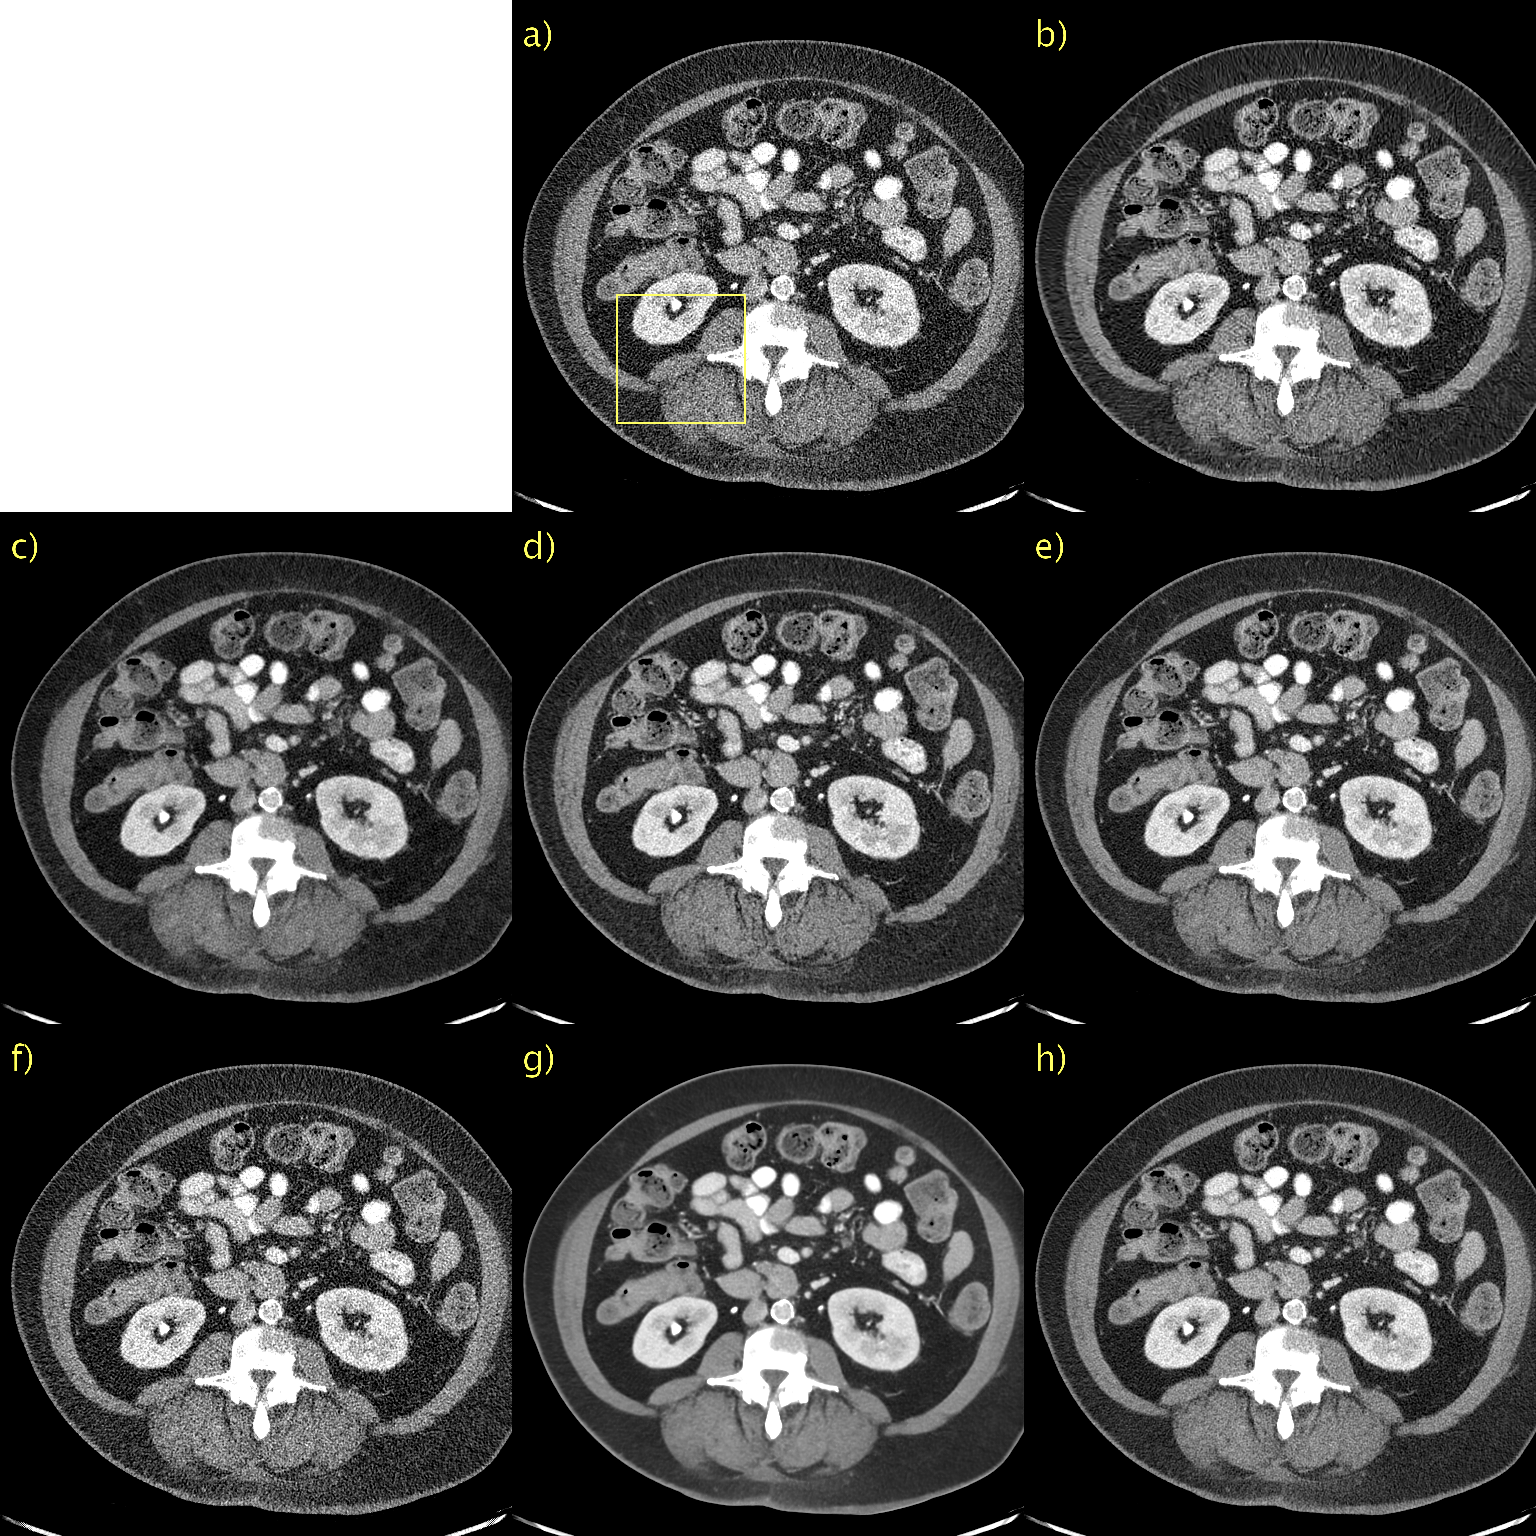

Qualitative results, alongside LPIPS, SSIM, and PSNR, for a representative slice from the Mayo low-dose CT validation data appear in Fig. 1. For the sake of brevity, we show results for the proposed method only for D𝐷D\rightarrow\infty and, best performing, D=128.𝐷128D=128. The former is included as an interesting case since it corresponds to a diffusion model, instead of PFGM++. This patient has a metastasis in the liver and we have included a magnification of this region of interest (ROI) in Fig. 2. a) and b) show the NDCT and LDCT images, respectively for reference. BM3D, shown in c), performs well in terms of noise suppression whilst preserving salient details. Nevertheless, this comes at a cost of artifacts that make the image appear a somewhat smudgy. WGAN-VGG, CD, and PPFM, all supervised methods, shown in d), e) and f), all suppress noise effectively and keep key details intact. We have overlaid a yellow arrow to point out a detail that appears in CD, shown e), but in none of the other images, including NDCT and LDCT. It appears that CD has added a feature into the image that appears realistic, but which we know is not genuine, given that we have the LDCT and NDCT images as reference. Such inaccurate removal or addition of details is loosely referred to as hallucination [2]. Noise2Void, shown in g), seems to in essence reproduce the LDCT image. However, quantitatively there is a marginal improvement. However, as shown in i), the proposed method (with D=128𝐷128D=128) effectively suppresses the noise whilst keeping salient features intact. Qualitatively, it is difficult to discriminate between the proposed method with D=128,𝐷128D=128, which is an unsupervised method, and PPFM, shown in f), a supervised method. Quantitatively for this particular slice, we can see that PPFM performs slightly better. Comparing D𝐷D\rightarrow\infty, shown in h), with D=128𝐷128D=128 in i) demonstrates the performance gains afforded by the PFGM++ framework. In particular, the proposed method with D𝐷D\rightarrow\infty appears over-smoothed and somewhat blurred.

Figure 1: Results on the Mayo low-dose CT dataset. Abdomen image with a metastasis in the liver. a) NDCT, b) LDCT, c) BM3D, d) WGAN-VGG, e) CD, f) PPFM, g) Noise2Void h) D𝐷D\rightarrow\infty i) D=128𝐷128D=128. Yellow box indicating ROI shown in Fig. 2. 1 mm-slices. Window setting [-160,240] HU.

Figure 2: ROI in Fig. 1 magnified to emphasize details. a) NDCT, b) LDCT, c) BM3D, d) WGAN-VGG, e) CD, f) PPFM, g) Noise2Void h) D𝐷D\rightarrow\infty i) D=128𝐷128D=128. Yellow circle added to emphasize lesion. 1 mm-slices. Window setting [-160,240] HU.